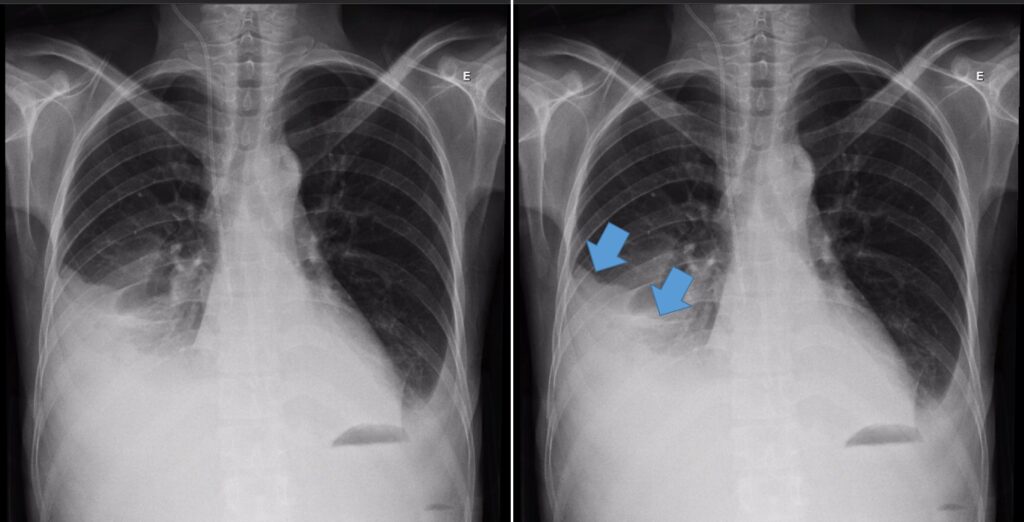

Derrame pleural é o acúmulo anormal de líquido no espaço pleural. Os principais sinais na radiografia são:

1. Imagem hipotransparente formando uma parábola;

2. Velamento do seio costofrênico;

3. Apagamento do contorno do diafragma e do coração;

4. Desvio do mediastino para o lado oposto quando volumoso;